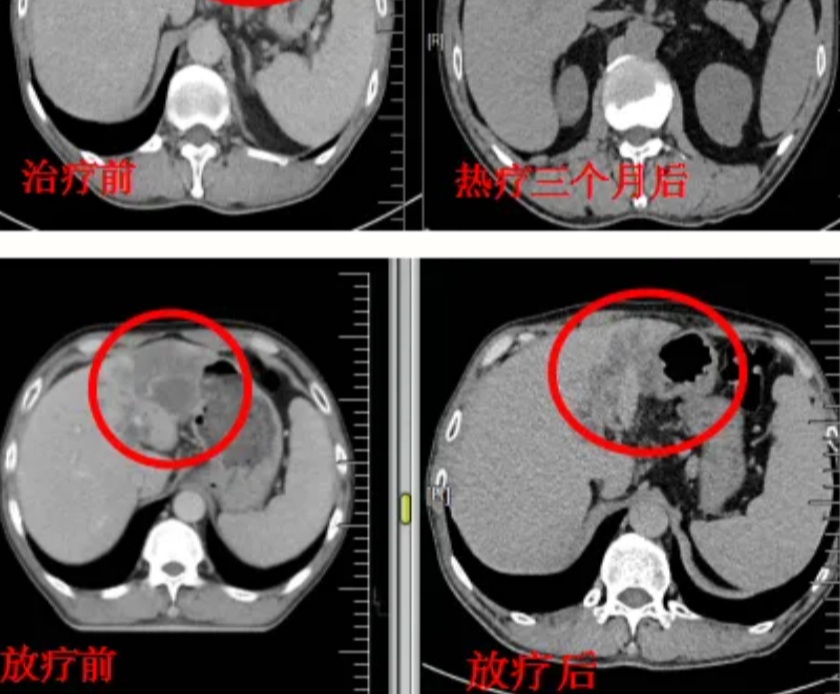

肝脏肿瘤:治疗原发性肝癌或转移瘤,保护正常肝组织。

射波刀治疗案例